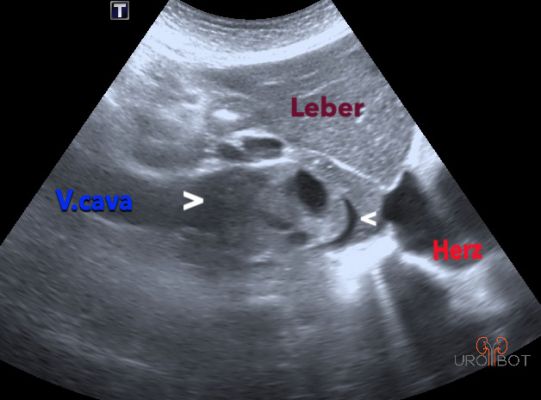

Video Tumorthrombus von Dr. Müller

Das Video zeigt eine sonographische Untersuchung der rechen Seite mit Nachweis eines großen Tumorthrombus in der unteren Hohlvene.